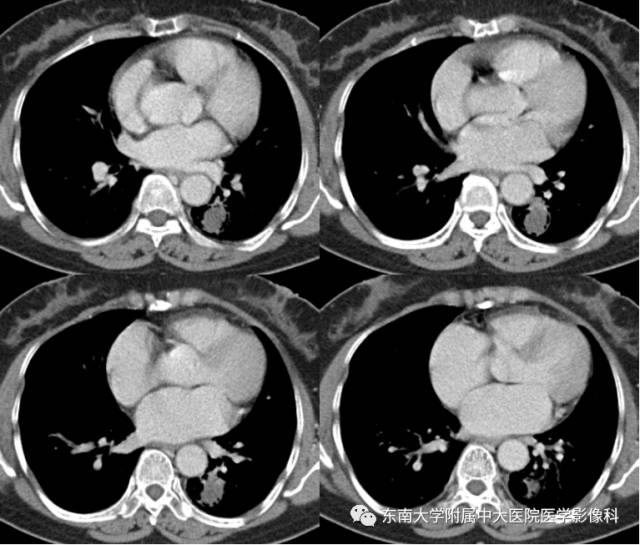

【病例】左下肺支气管囊肿伴肺曲霉菌感染

女,61岁,因“体检发现左肺占位1月余”入院。

CT